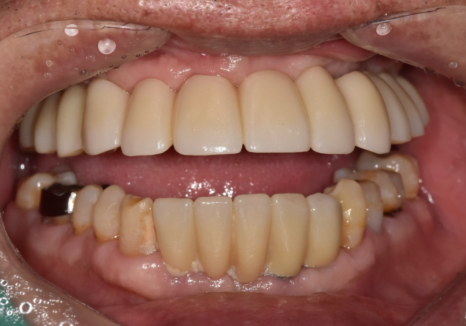

무치악 환자분의 보철은 오히려 더 까다롭습니다.

뼈가 없어서 안 된다구요? 70대 당뇨 무치악 환자분의 전체 임플란트 사례

치아가 있으면 높이 기준점이 있는데,

무치악은 기준점이 없기 때문에

적절한 얼굴의 높이(수직고경)를

새로 찾아야 하거든요.

너무 높으면 턱이 아프고,

낮으면 씹는 힘이 약해집니다.

그래서 이 환자분의 경우,

적절한 기준점에 맞게

임시 치아를 충분히 써보시게 했습니다.

임시치아를 써보시며

불편한 부분은 없었는지 확인하고,

안모 변화를 확인한 뒤에야

최종 보철을 완성했습니다.